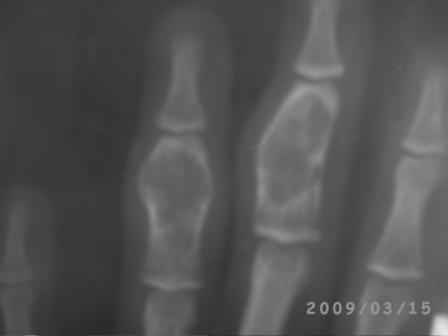

Уважаемые коллеги, на осмотре девочка 2006 г.рожд. Со слов матери 3мес. назад заметила припухлость основного фаланга 3-пальца, которая постепенно увеличилось до настоящего размера где-то в течении месяца, не болит, ребенка не беспокоит, признаки воспаления отсутствуют. Консультация онколога, биопсия - опухоль исключена (со слов матери), фтизиоортопед - тбс исключен. От основной фаланги 3 пальца к головке 4-пястной кости под кожей прощупывается хрящевидная ткань. Р-граммы от 10 декабря и 15 февраля, и фото прилагается. Что делать? Уважаемые коллеги, помогите! С уважением Абдурашид.

Добрый день, уважаемый Абдурашид. Судя по рентгенограмме, к сожалению не очень качественной, речь может идти о варианте дисхондроплазии, которую обозначают, как солитарную хондрому. Рентгенологически они проявляются в 3 вариантах-в виде интрамедуллярно и центрально расположенной энхондромы с вертеннобразным вздутием диафиза изнутри и истончением кортикальной пластинки, в виде опухоли, расположенной эксцентрично с заполнением части кортикального слоя и характерным костным козырьком, в виде экхондром, выступающих за пределы кости

Уважаемый Игорь Владимирович! Я очень рад Вас услышать! И в самом деле это один из вариантов дисхондроплазии ( т.н. болезнь Оллье), так как принесли результат биопсии: -"эмбриональный хрящевой ткань, симулирующий хрящевую опухоль"

Планируем операцию экскохлеацию и выскабливанию с максимальным сохранением футляра из надкостницы и ростковую зону и тампонада с аутостружкой.